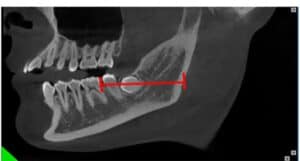

A Cone Beam CT is compiling 3D data, but it still allows us to access it only through 2d representations (slices) in a flat 2D screen. The surgeon has to read these combined 2D images and reconstruct a mental 3D structure of the surgical anatomy, certainly not an easy task to do with precision.

A Challenging surgical case with a complex of vertical and horizontal septa in the posterior sinus. Segmentation of the 3D radiographical and optical data and 3D printing in multiple layers from AMMA Ltd Hong Kong, has allowed for an accurate representation of the anatomy where multiple surgical access approaches were tested.